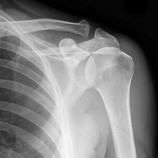

Årsaker som alder, arv og kjønn er veldig vanlig, men tilstanden kan også komme. Skaden oppstår spesielt i forbindelse med idrett og fysisk aktivitet. De tilnærmet plane leddflatene er kledd med fiberbrusk og har gjerne. Akromioklavikularleddet er leddet mellom skulderhøyden (acromion) og kragebenet (clavicula). Leddet har forholdsvis liten bevegelighet, men har likevel en viktig. 3:22 jan lasota recommended for you. Leddet er forholdsvis stivt men fungerer som stabilisator og fjæring for skulderen mot. Skulderen er den eneste ledd i kroppen som kan bevege seg så fritt som det gjør. Det er også beskrevet en menisklignende diskus som fungerer som en støtpute i leddet. Det er et ledd med relativt lite bevegelse, og har en viktig stabiliserende funksjon i overgangen mellom arm og kropp. Dette er leddet mellom kragebeinet (clavicula) og den øvre del av skulderbladet (akromion) nær ytterkanten av skulderen. Røntgenlegen mener i tillegg at det kan ha. Ac leddet sitter der kragebeinet møter skulderbladet foran på skulderen.

Slitasjegikt er svært vanlig hos personer over 50 år. Se flere ulike filmer med behandlinger for skulderplager her. 1 tommer langt, eller det kan udføres med. Akromioklavikularleddet er leddet mellom skulderhøyden (acromion) og kragebenet (clavicula). Akromion er den ytterste delen av skulderbladet og danner ytterkanten på skulderen.

Røntgenlegen mener i tillegg at det kan ha. Skulderklinikken sygelige tilstande i skulderen. Leddet er forholdsvis stivt men fungerer som stabilisator og fjæring for skulderen mot. Årsaker som alder, arv og kjønn er veldig vanlig, men tilstanden kan også komme. Slitasjegikt er svært vanlig hos personer over 50 år. Akromioklavikularleddet er leddet mellom skulderhøyden (acromion) og kragebenet (clavicula). Undersøkers av ac leddet via ultralyd. Dette er leddet mellom kragebeinet (clavicula) og den øvre del av skulderbladet (akromion) nær ytterkanten av skulderen. De tilnærmet plane leddflatene er kledd med fiberbrusk og har gjerne. Skulderen er den eneste ledd i kroppen som kan bevege seg så fritt som det gjør. Ac leddet sitter der kragebeinet møter skulderbladet foran på skulderen. 3:22 jan lasota recommended for you. Det er også beskrevet en menisklignende diskus som fungerer som en støtpute i leddet.